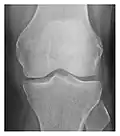

Figure 1: A 56-year-old woman presenting with left knee pain after a fall. (a) Initial anteroposterior radiograph was considered normal, however, subtle cortical disruption of the anterior rim of the medial tibial plateau, medial to the tibial spine, is noted (arrow). (b) Coronal T1-weighted MRI confirms the cortical disruption (arrow) and shows extensive fracture through the proximal tibia. (c) Coronal proton density-weighted image with fat saturation shows extensive edema in the subchondral bone. Note also hypersignal adjacent to the medial collateral ligament corresponding to a grade I sprain (arrowheads).[1]